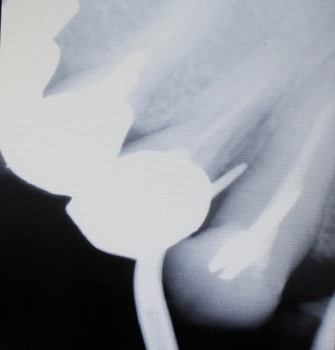

短針を挿入した像

かなり深い